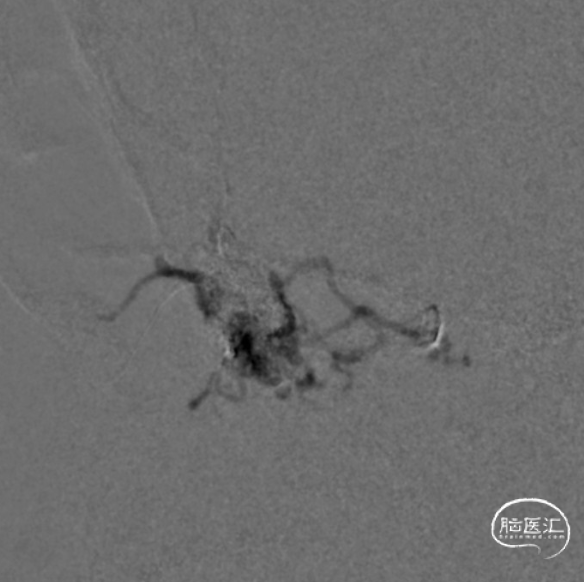

一期治疗

治疗经过